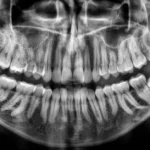

Plomba jest sztucznym materiałem, który z biegiem lat starzeje się, zmienia kolor, rozszczelnia się.

W efekcie, czego pojawia się silny kontrast kolorystyczny. Wypełnienie staje się widoczne, przybiera ono często postać matowych, szarych lub białych plam. W naszym gabinecie oferujemy najnowocześniejszy materiał kompozytowy do estetycznej odbudowy zębów.

Odbudowa niewielkich ubytków w obrębie szkliwa należy do największych i najtrudniejszych wyzwań w stomatologii estetycznej. Enamel HRI to przełomowa technologia, gdzie współczynnik załamania światła w materiale (1,62) jest identyczny z naturalnym szkliwem. Pod względem właściwości optycznych i estetycznych żaden inny kompozyt nie posiada nawet zbliżonych właściwości. Rezultatem są niewidoczne i bardzo naturalne wypełnienia bez widocznej granicy przejścia, bez efektu szarości, a wszystko to w oparciu o naprawdę szybką i prostą technikę pracy.